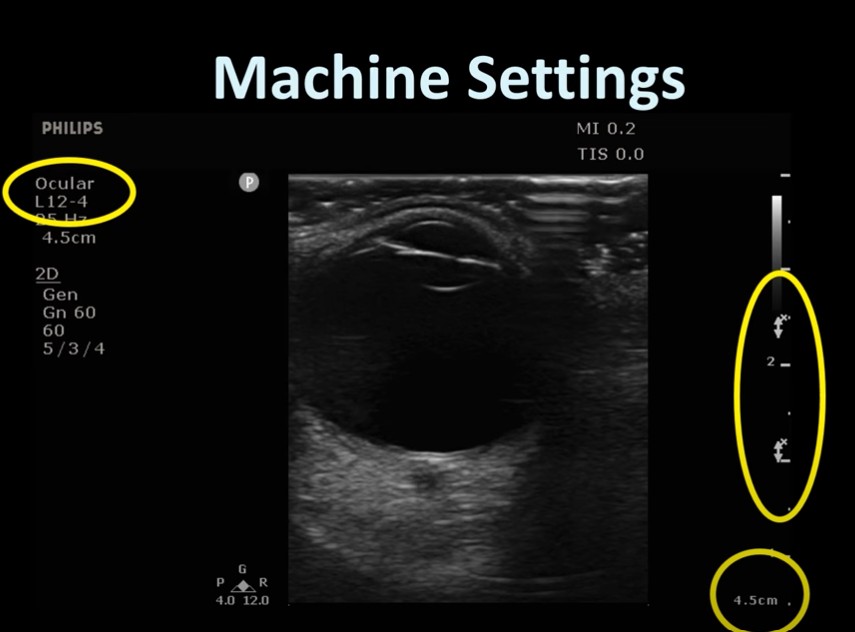

Apr 25, 2025 Guardians of the Sound2:263:554:025:29 Very important to anchor your arm on the shoulder [see right picture] to avoid putting any pressure on the globe]. Review transcript on YouTube 5:39 – 6:166:277:16 In both views the patient is asked to look right and left and up and down.7:367:56 You need an ophthalmology setting on your machine so that you don’t exceed the safe TI and MI.8:018:328:459:029:119:5710:2910:3610:4010:4511:1211:3511:5012:4013:05 Warning Use only eye settings. Don’t use the MSK setting in the picture below: